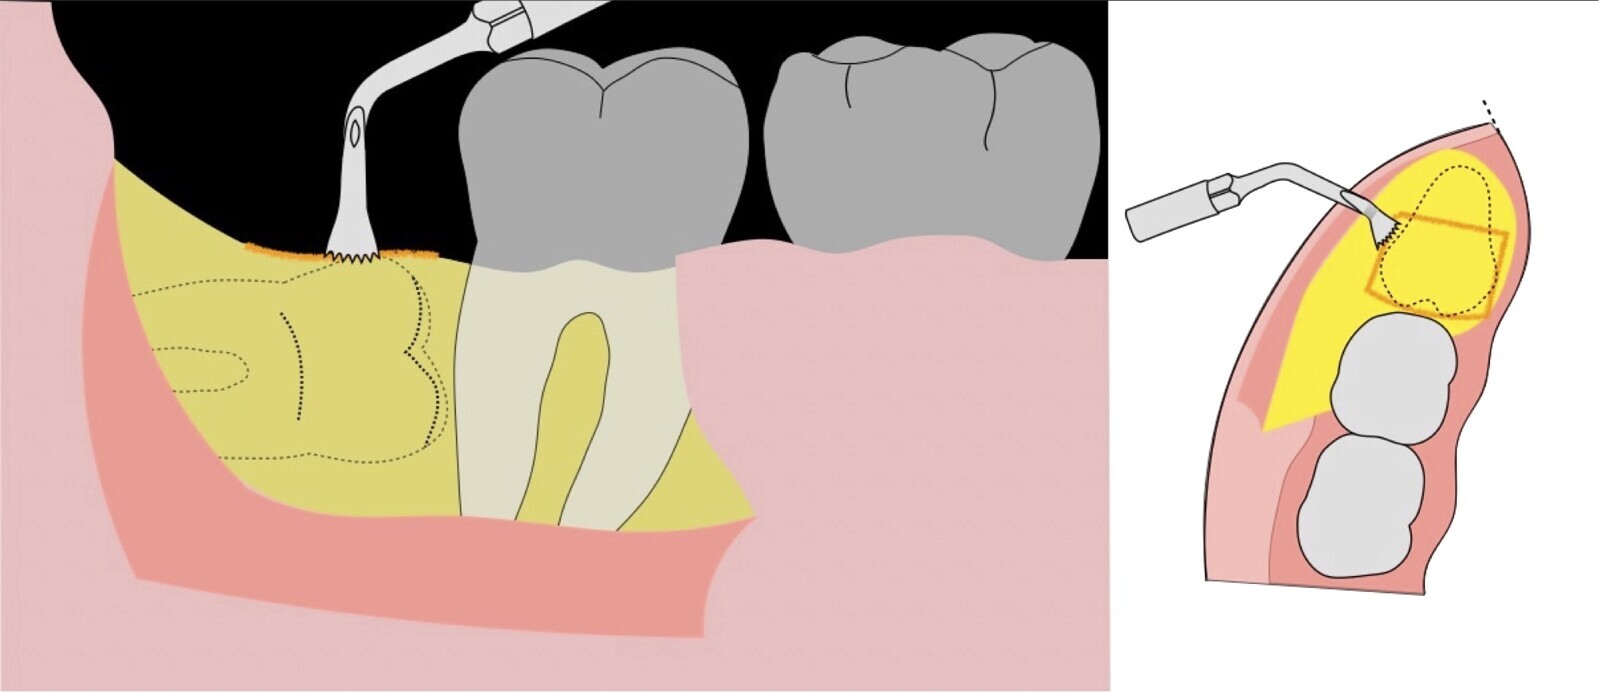

Figura 20. Retirada del segundo fragmento óseo (a). Ampliación de la ventana ósea con el inserto plano de corte de punta aserrada (b).

Figura 21. Ampliación de la ventana ósea con el inserto plano de corte de punta aserrada (a). Extirpación de tejido blando remanente con inserto de corte y coagulación del electro bisturí (b). Exposición de la corona clínica de la pieza 3.8 (c).

Figura 22. Ampliación de ventana ósea distal con inserto plano de corte de punta aserrada (a). Desplazamiento distal de pieza 38 con botador recto convencional (b).